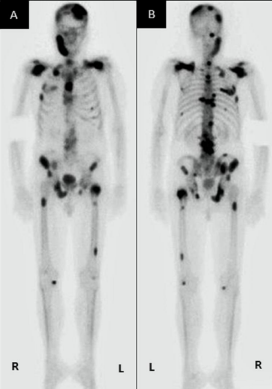

The attending oncologist was informed of the metastatic finding. Following this, the patient underwent a computed tomography (CT) scan and isotope bone scan (see Figure 5A and 5B) which demonstrated

multiple bone metastases to his sternum, ribs, ilium, femur, and vertebrae as well as his mandible. Subsequently, patient received chemotherapy treatment. Nevertheless, three months later, unfortunately, the patient died as a sequel of hi tumour.

Figure 5: Bone scan images (A) anteroposterior view and (B) posteroanterior view showing multiple distant bone metastases to the mandible, sternum, ribs, ilium, femur and vertebrae. Reproduced from: [12] under the Creative Commons Attribution License.